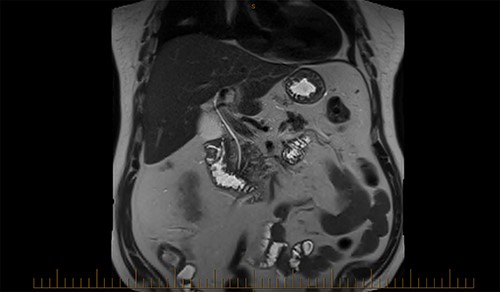

Patient SC is a 72-year-old lady who presented with urosepsis secondary to a left-sided distal ureteric renal stone. Her medical history includes ischemic heart disease, chronic pulmonary obstructive airway disease, type 2 diabetes mellitus, Parkinson’s disease and a previous open cholecystectomy. She was admitted to the intensive care unit and a left-sided nephrostomy tube was inserted. Initial CT imaging incidentally identified a ‘bread clip’-shaped FB in the distal jejeunum (Figs 1 and 2). There was no evidence of obstruction nor perforation. Abdominal X-rays failed to show the presence of a FB.

The acute surgical unit team consulted the patient and initial conservative management included keeping a stool diary and trialling 1 L of glycoprep. Unfortunately, serial imaging failed to show any meaningful progression of the FB. After a successful antegrade ureteric stent insertion, the patient recovered from urosepsis and a decision was made to proceed with a laparoscopic small bowel resection to retrieve the FB.

Intraoperatively, an inflamed segment of 5 cm of the mid jejunum was identified, the FB was palpable and appeared to be partially eroding through the serosa. A SB resection was performed with primary stapled anastomosis. The FB was identified as a BC.